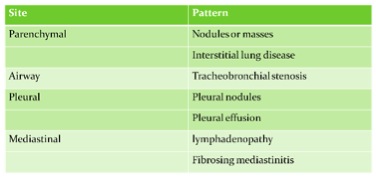

There is still no published consensus about the diagnostic criteria of igG4-related disease. Most studies are using diagnostic criteria by Umehara and colleagues in 2011: 1) clinically showing characteristic diffuse or localized swelling or masses in single or multiple organs, 2) hematological examination shows increased serum IgG4 concentration, 3) histopathologic examination showing a) marked lymphocyte and plasmacytic infiltration and fibrosis, and, b) infiltration of IgG4 + plasma cells: ratio of IgG4+/IgG+ cells more than 40% and more than 10 IgG4+ plasma cells per high power field. Patient can be diagnosed as definite (fulfill all 3 criteria), probable (fulfill the 1st and 3rd criteria), and possible (fulfill the 1st and 2nd criteria) IgG4-related disease (3). According to 2 series from Japan, the incidence of lung involvement of IgG4-related disease can range from 14 to 54% (4,5). There are two relatively large scale case series published by Matsui S in Respirology 2013 and Zen Y in Am J Surg Pathol 2009 to describe the clinical features of patients with IgG4-related lung disease. Both series showed male predominance around 80%. There were 12% and 43% of patients in respective series having allergic history like rhinosinusitis and asthma. Only 28% and 47% of patient in respective series having pulmonary symptoms and mostly complained cough. The radiological features of lung manifestation were described in Zen study, which can be nodular, bronchovascular interstitial, ground-glass opacity or pleural lesion. (table 2,3) The possible radiological findings of IgG4-related lung disease were also described in review article by Ryu in Eur Respi J 2012 (table 4) (6).